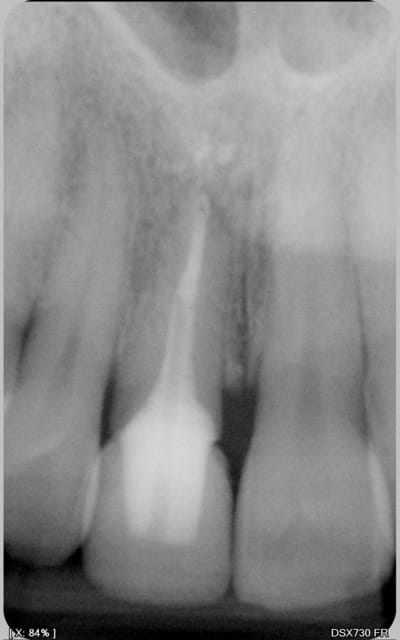

logement canalaire au largo 3, puis machtou vert chauffé au chalumeau.

Radio cône en place avant de le sceller, avec un bon tuck- back et le machtou chauffé au rouge il est rare que le cône reste collé au fouloir. L'avantage de faire la provisoire dans la séance permet de descendre la couronne en plateau et de bien visualiser la chambre pulpaire, particulièrement indiqué dans le cas ci dessus sur des 31 41 d'une personne âgée pulpe rétractée ou à force de la chercher tu trouves .... le desmodonte !))))).